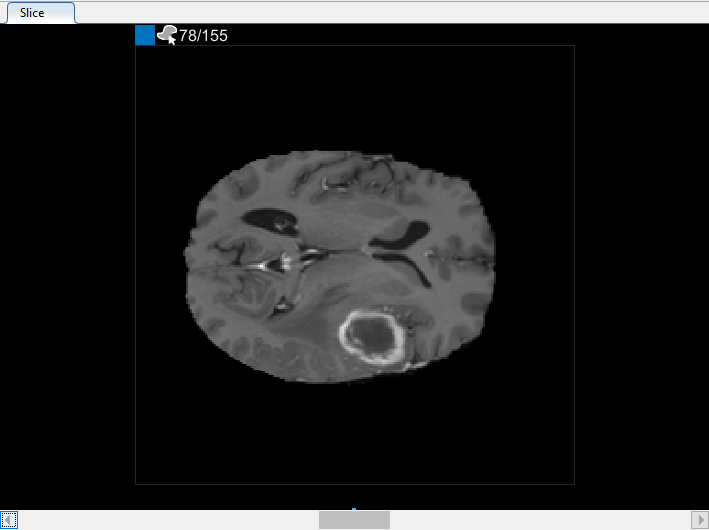

В 3-D панели Отображения можно вращать объем, чтобы исследовать данные с разных сторон, с помощью мыши. Можно также настроить отображение объема в 3-D вкладке Display в панели инструментов приложения. Например, если у вас есть метаданные, что descibes относительный размер вокселей, можно задать его в Пространственной части Ссылки 3-D вкладки Display в панели инструментов приложения. Чтобы улучшить ваше представление данных, можно изменить цвет фона, используемый в 3-D отображении, изменить порог и непрозрачность отображения, и включать оси ориентации с отображением, как показано в этом рисунке. С мозговыми данными MRI вы видите опухоль в височной доле, которую вы хотите сегментировать.

Можно также просмотреть каждый срез объема в панели Среза. Используйте ползунок в нижней части панели, чтобы переместиться от среза до среза. Вы видите опухоль на срезе 35 через срез 88. По умолчанию панель Среза отображает объем, ориентированный вдоль оси X-Y, но можно изменить это использование кнопки в разделе Orientation панели инструментов на вкладке Segmenter. Панель Среза также, где вы используете инструменты для рисования, чтобы задать маску.